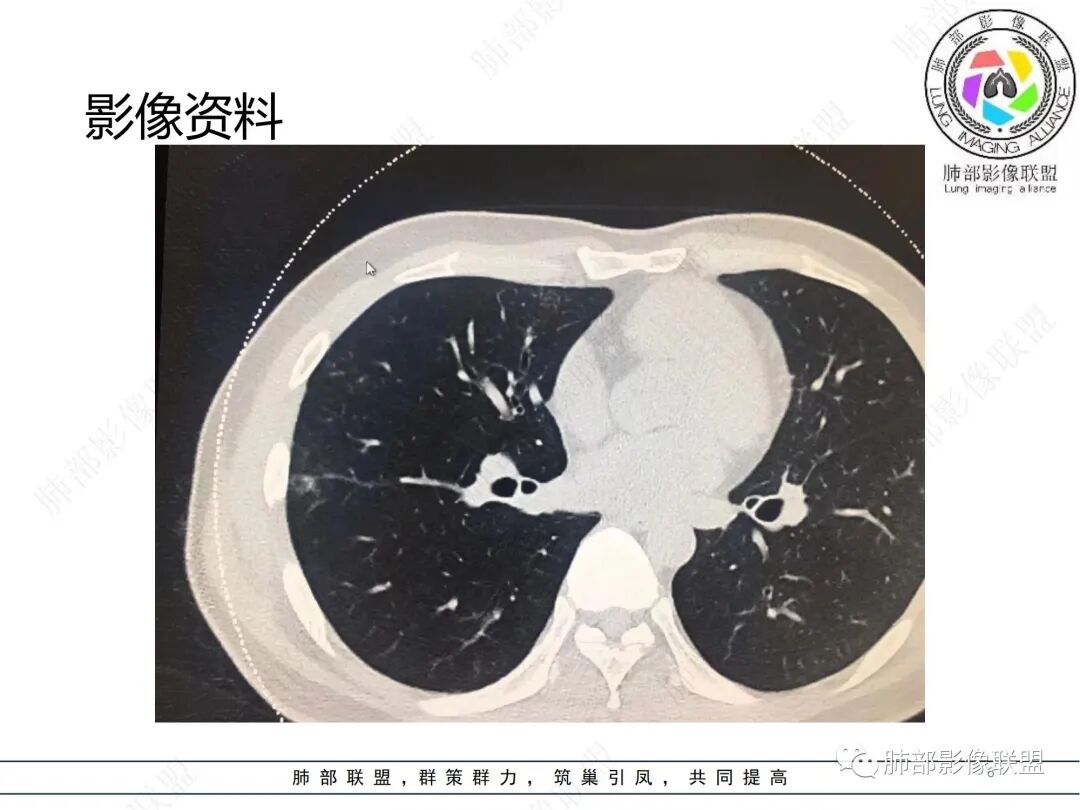

中年男性,体检发现肺部阴影,无症状和特异性检验结果。胸部CT提示双肺多发实变和磨玻璃影,胸膜及肺门处均有分布,实变内部匀实,有支气管通入,边缘平直刀切,实变周围有磨玻璃影和小的树芽。强化后均匀的强化。纵隔内未见肿大的淋巴结。考虑炎性改变,渗出+增生,机化性改变。具体机化的原因,不能明确,慢性感染?鉴别隐球。暂不考虑肿瘤或结核病。

男性,37岁,体检发现,双肺多发斑片状实变影伴周围磨玻璃影,右肺为主,胸膜下多发,部分支气管进入后截断,轻度强化,考虑OP或隐球菌感染可能

男,37,体检发現双肺阴影2周。胸部CT:双肺多发斑片状阴影,实变/GGO,晕征,支气管进入后堵塞,部分可见小叶内间隔增厚。右肺多,胸膜下为主,支气管束周围也有。轻度强化,考虑:OP?病毒感染?鉴别血管炎、淋巴瘤等。

男性,37岁,体检发现双肺阴影2周,实验室检查,指标正常。穿刺活检证实为:粘膜相关淋巴组织型边缘区B细胞淋巴瘤。本例MALT,群内各位老师基本都在OP、隐球菌之间徘徊,和图像太少,没有重建图像有一定关系,对错并不重要,重要的是我们通过这个病例学到了什么?我们不妨学习一下这几个病。

双肺多发片状影及结节影,沿胸膜下或血管支气管束分布,边界可分辨,实性密度或磨玻璃密度,部分为实性密度见磨玻璃晕,支气管出入,部分轻度扩张。病灶内小叶间隔增厚,脊柱旁病灶表现相当明显,病灶具有一定程度张力,未见空洞或钙化,未见新旧不等。

具有相当范围病灶却缺乏临床表现—用普通感染难以解释。

间质改变明显,具有一定收缩力,穿行支气管扩张—病灶存续时间较长,应想到新生物存在的可能性,如MLAT淋巴瘤等,尤其是较长时间复查病灶未见明显变化或逐渐进展时。